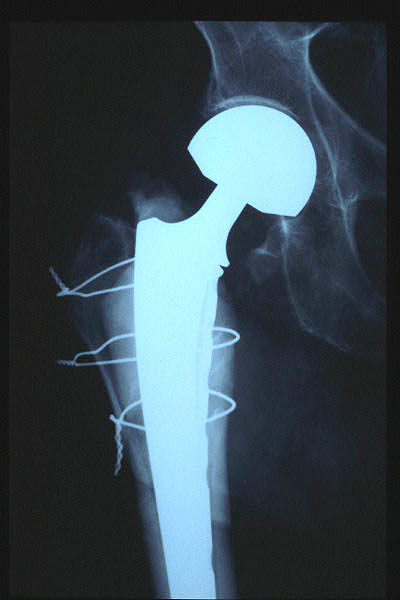

Fractura cuello fémur. Prótesis completa.

Fractura intertrocantérea de fémur, osteosíntesis

Fractura de fémur, prótesis parcial de cadera